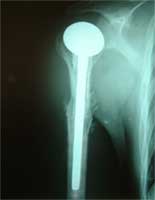

肱骨近端软骨肉瘤,肿瘤段截    大段异体骨人工肱骨头置换术后3年